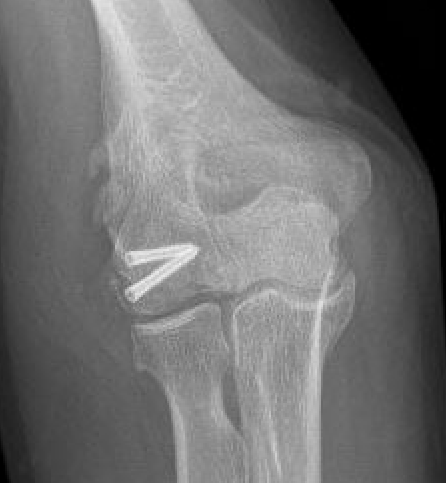

Coronal shear fracture of the distal humerus

Capitellum +/- trochlea

Bryan & Morrey Classification

| Type I | Type II |

|

Large osseous fracture of the capitellum

Articular cartilage injury with little bone |

Hanh Steinthal fracture

Kocher Lorenz fracture |

| ORIF | Typically remove |